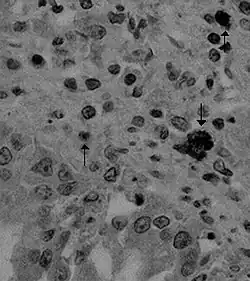

Es causada por el coronavirus Alphacoronavirus 1. El virus invade y se replica en las vellosidades del intestino delgado.[1]